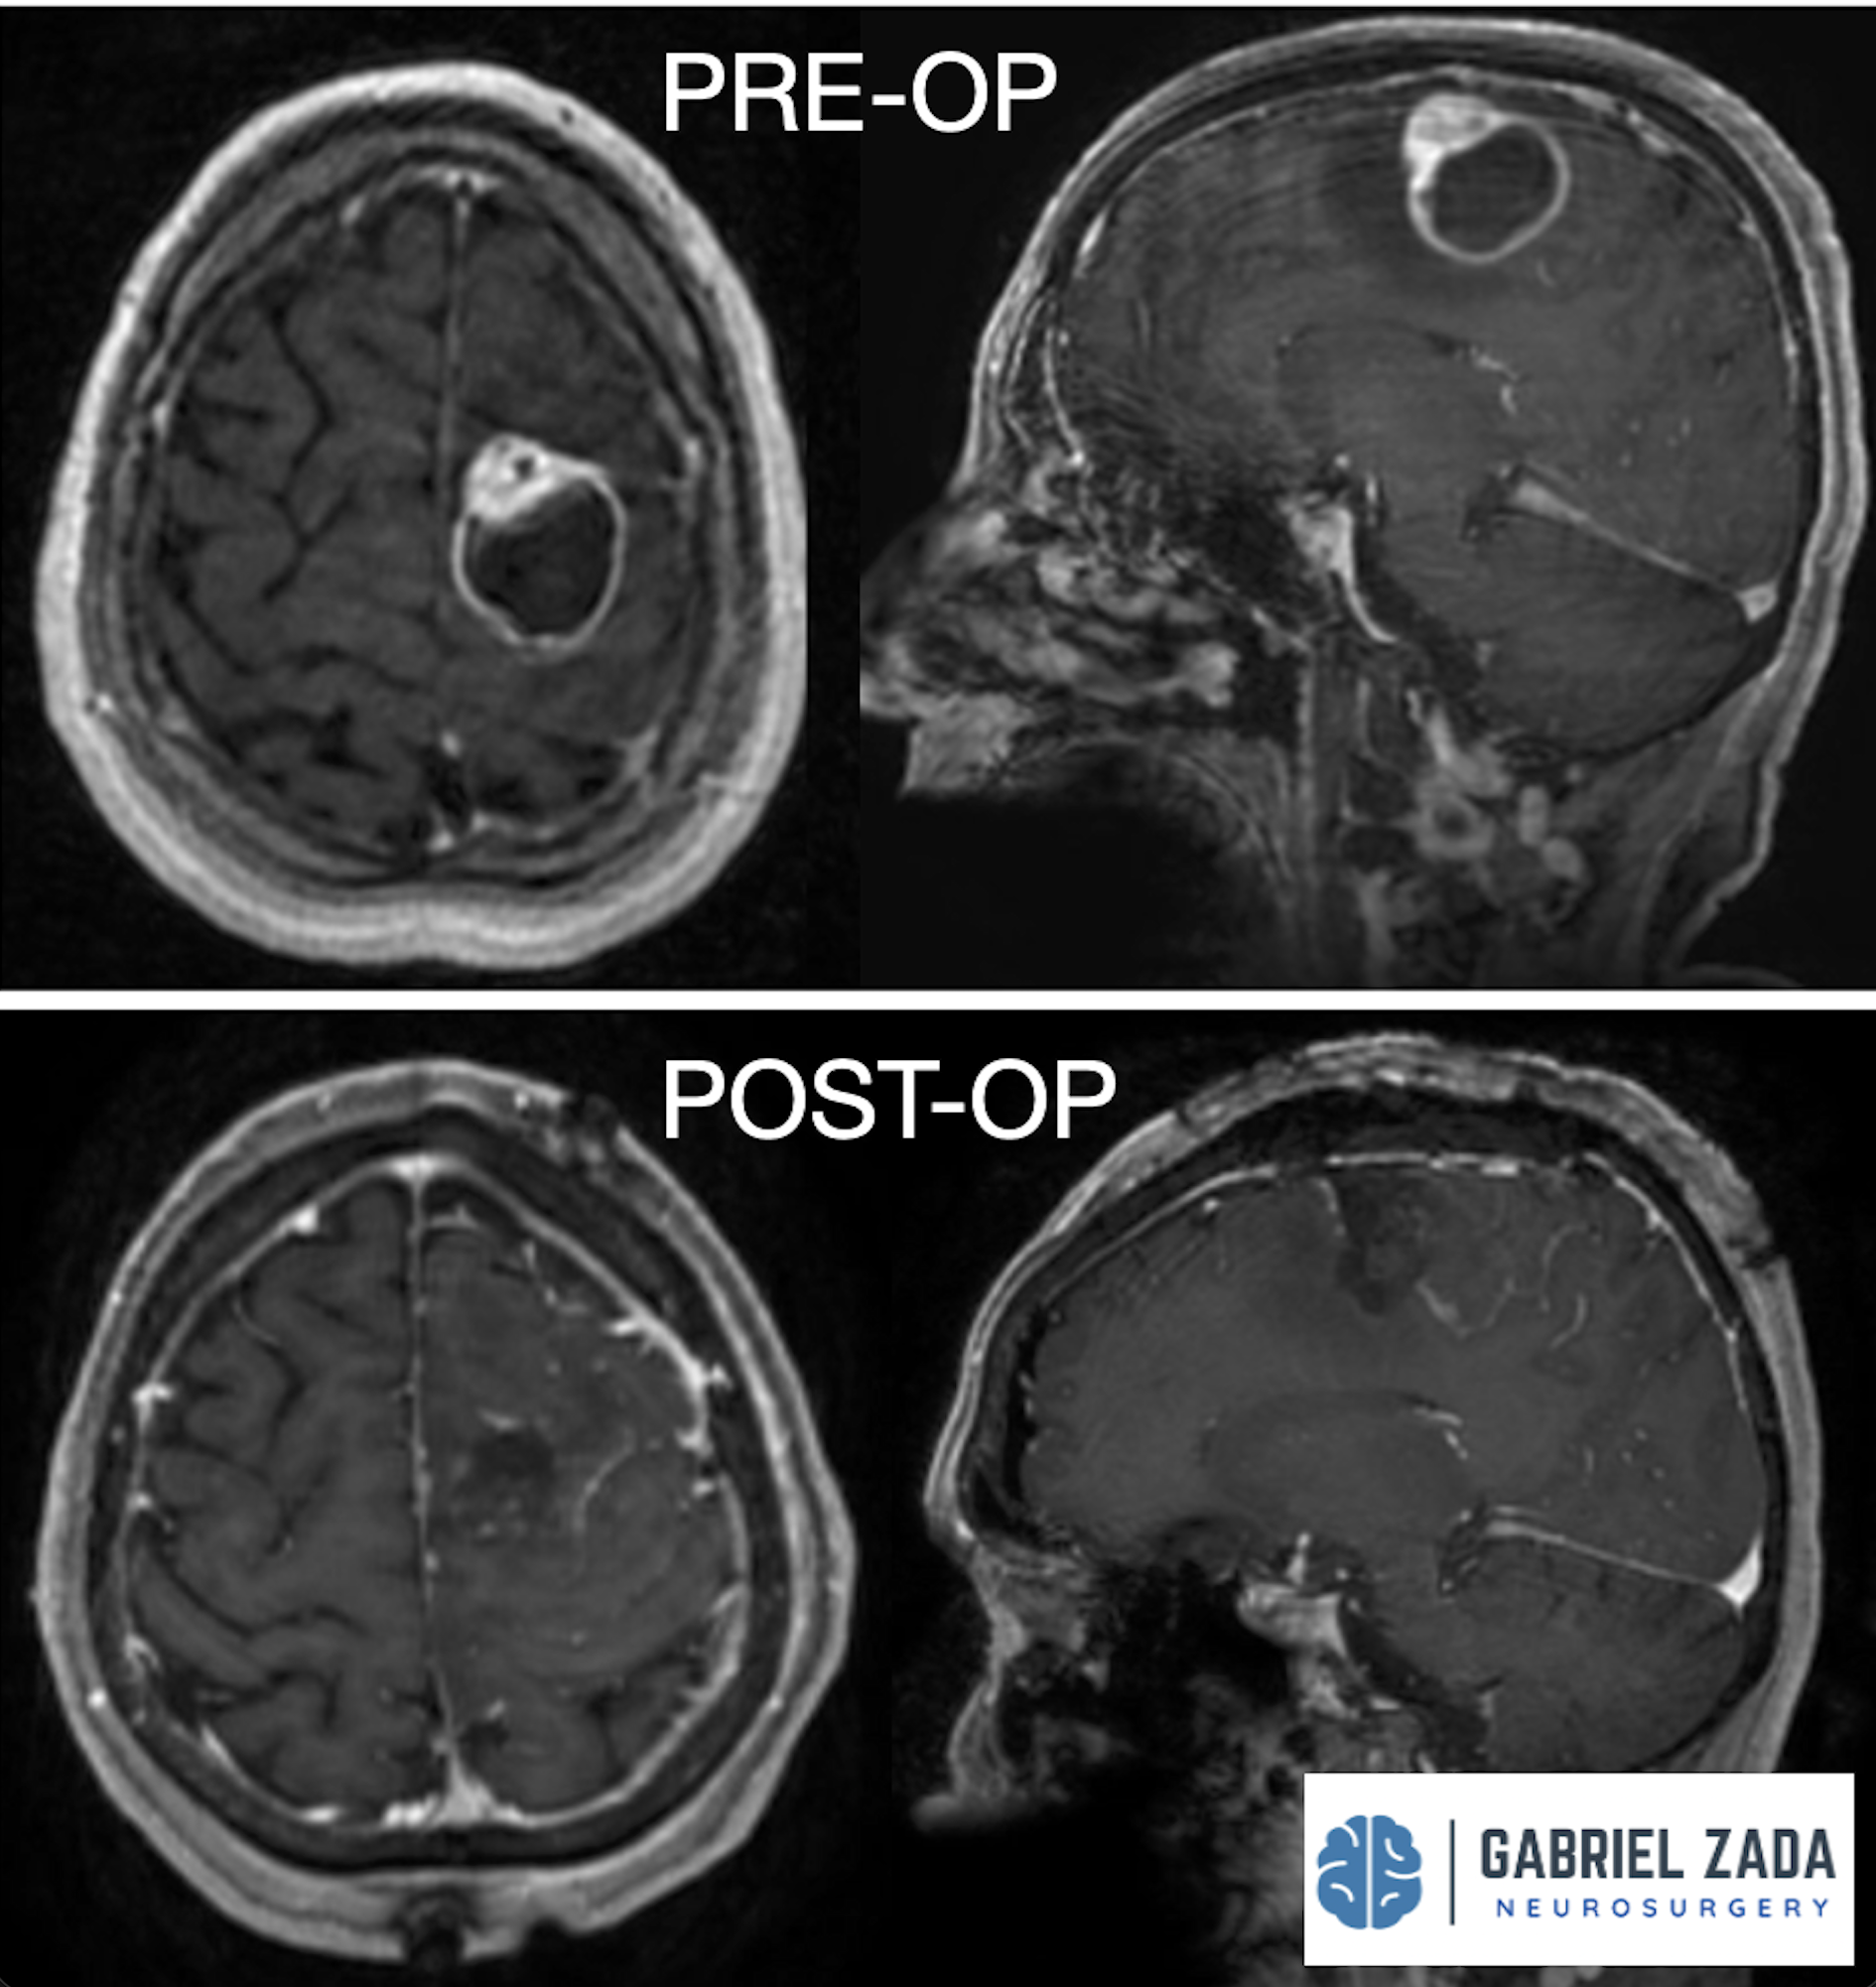

Explore this comprehensive gallery featuring pre‑ and post‑operative imaging of patients with skull‑base tumors treated by Gabriel Zada, MD, MS, FAANS, FACS. These cases highlight Dr. Zada’s expertise in advanced neurosurgical techniques and outcomes.

*Representative cases shown for educational purposes. All images de-identified. Individual results vary.